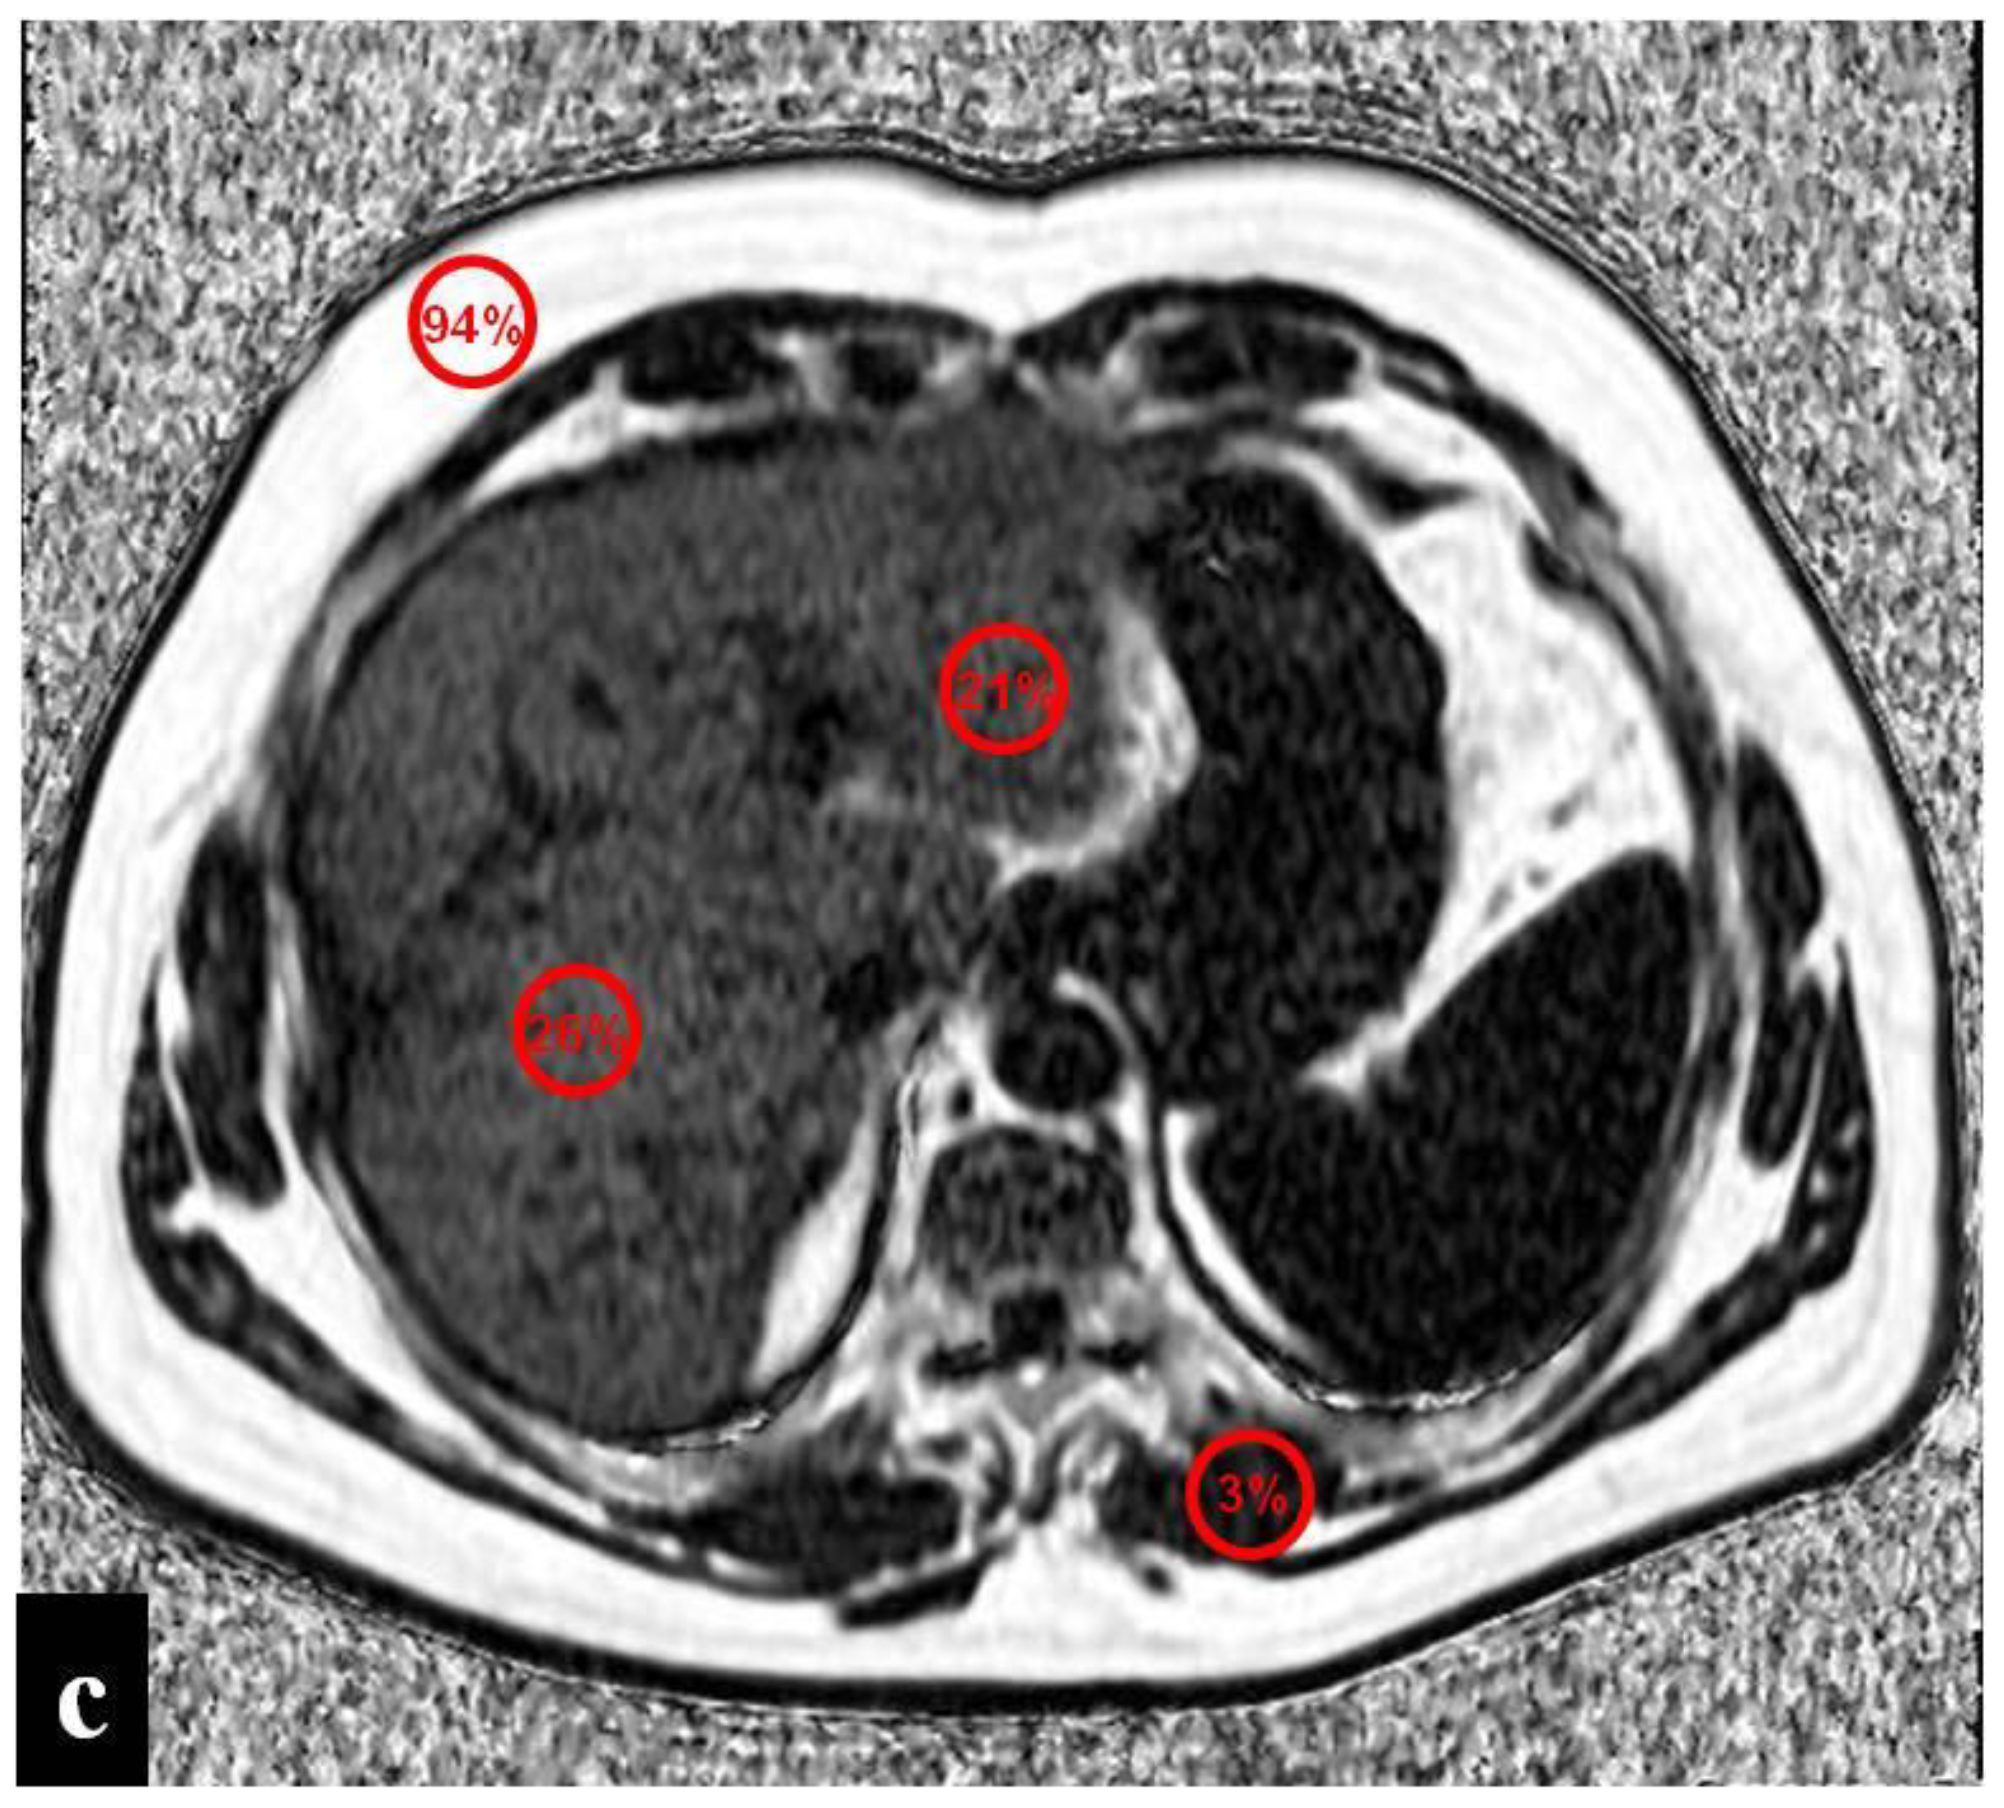

3. Sinusoidal Obstruction Syndrome (SOS)

- Bannas, P.; Kramer, H.; Hernando, D.; Agni, R.; Cunningham, A.M.; Mandal, R.; Motosugi, U.; Sharma, S.D.; Munoz del Rio, A.; Fernandez, L.; et al. Quantitative magnetic resonance imaging of hepatic steatosis: Validation in ex vivo human livers. Hepatology 2015, 62, 1444–1455. [Google Scholar] [CrossRef] [PubMed]

- Hines, C.D.; Frydrychowicz, A.; Hamilton, G.; Tudorascu, D.L.; Vigen, K.K.; Yu, H.; McKenzie, C.A.; Sirlin, C.B.; Brittain, J.H.; Reeder, S.B. T1 independent, T2* corrected chemical shift based fat-water separation with multi-peak fat spectral modeling is an accurate and precise measure of hepatic steatosis. J. Magn. Reson. Imaging 2011, 33, 873–881. [Google Scholar] [CrossRef] [PubMed]

- Idilman, I.S.; Aniktar, H.; Idilman, R.; Kabacam, G.; Savas, B.; Elhan, A.; Celik, A.; Bahar, K.; Karcaaltincaba, M. Hepatic steatosis: Quantification by proton, density fat fraction with MR imaging versus liver biopsy. Radiology 2013, 267, 767–775. [Google Scholar] [CrossRef]

- Idilman, I.S.; Keskin, O.; Elhan, A.H.; Idilman, R.; Karcaaltincaba, M. Impact of sequential proton density fat fraction for quantification of hepatic steatosis in nonalcoholic fatty liver disease. Scand. J. Gastroenterol. 2014, 49, 617–624. [Google Scholar] [CrossRef]

- Yoneda, N.; Matsui, O.; Ikeno, H.; Inoue, D.; Yoshida, K.; Kitao, A.; Kozaka, K.; Kobayashi, S.; Gabata, T.; Ikeda, H.; et al. Correlation between Gd-EOB-DTPA-enhanced MR imaging findings and OATP1B3 expression in chemotherapy-associated sinusoidal obstruction syndrome. Abdom. Imaging 2015, 40, 3099–3103. [Google Scholar] [CrossRef] [PubMed]